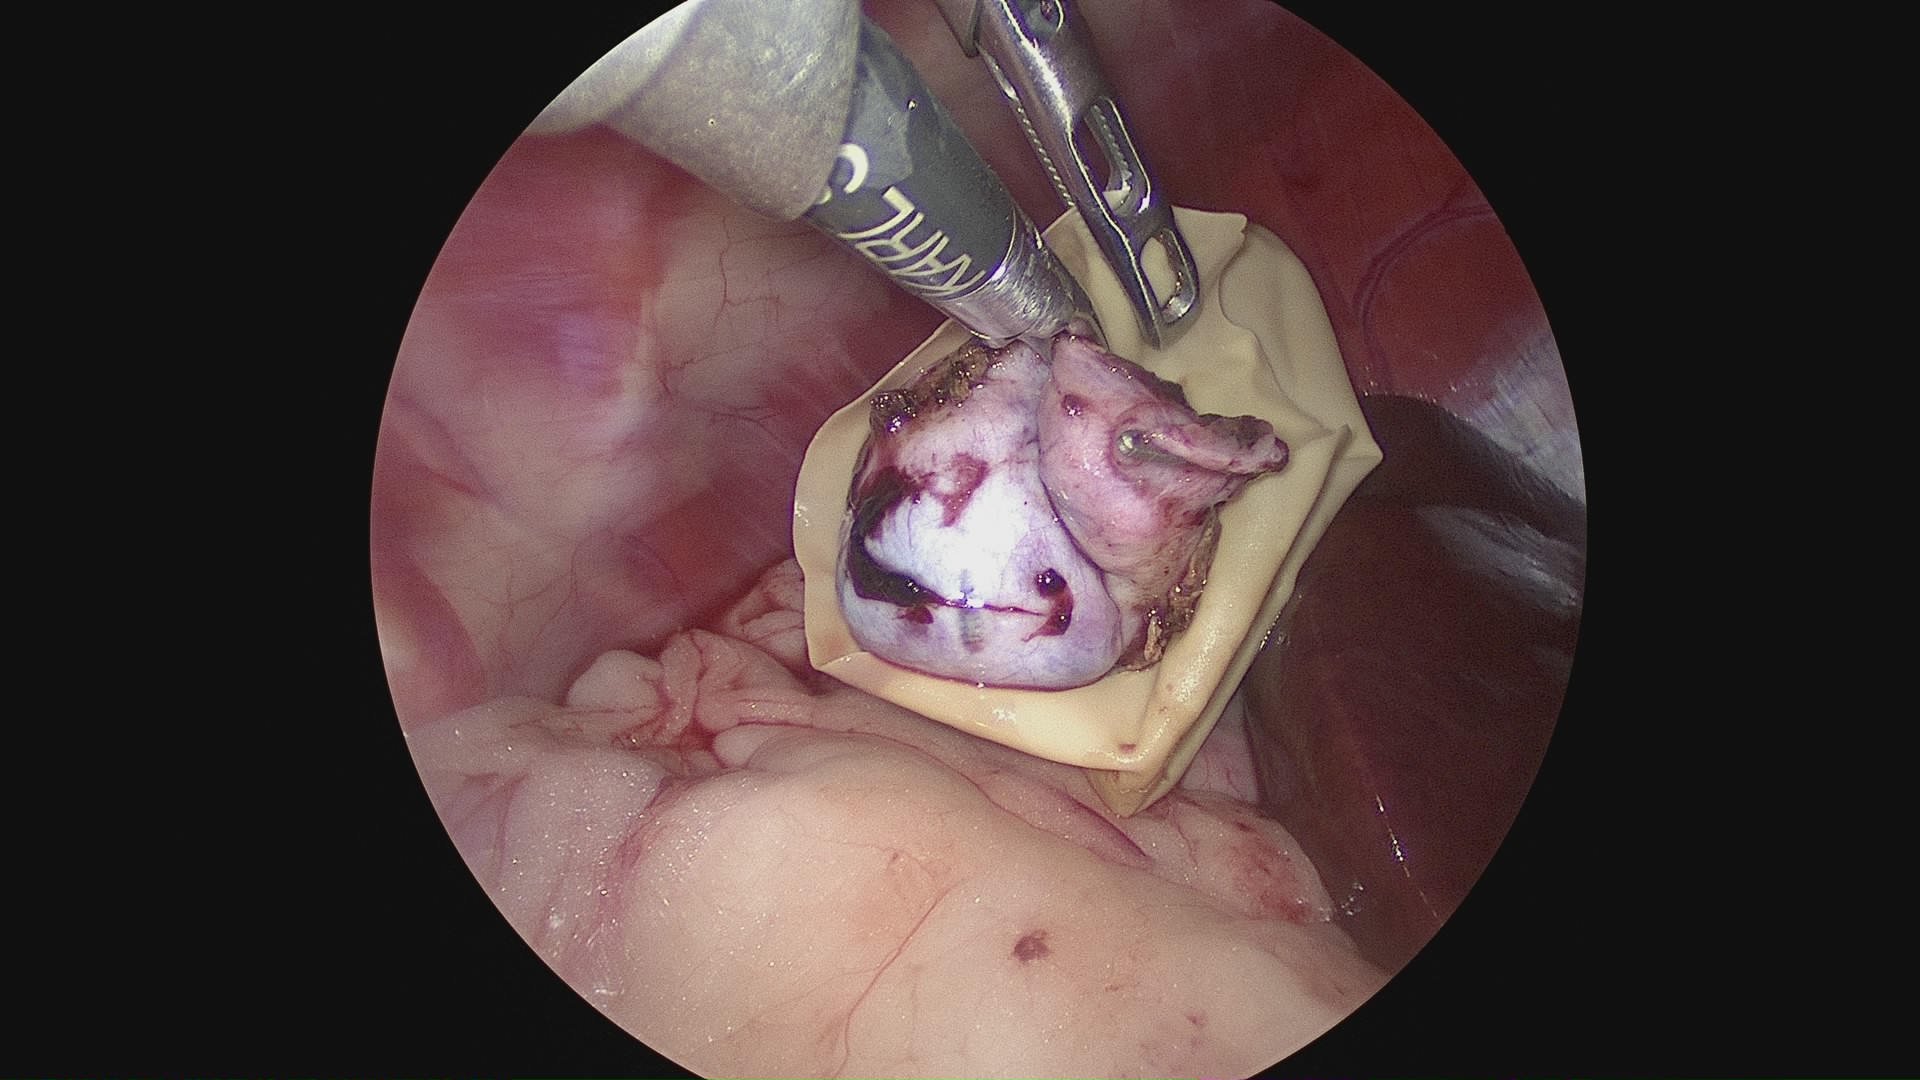

術前に行う超音波検査とCT造影検査により適応可能な場合は、腹腔鏡で胆嚢を摘出します

開腹手術と比べると傷が小さく、術後の回復が早い他メリットがいくつかあります

慢性炎症により肝臓への癒着が強い場合、胆嚢破裂を伴ったり、総胆管閉塞が強い場合は、開腹手術が適応になります。